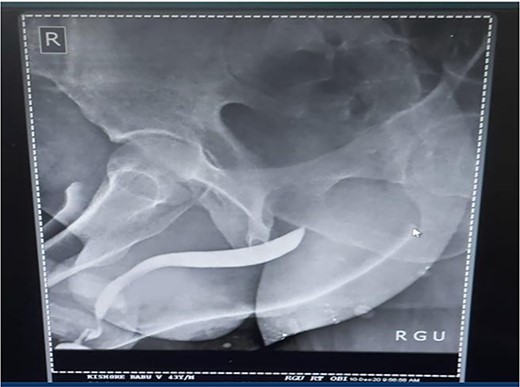

A 37-year-old male presented with a history of a ‘snap’ sound and immediate detumescence of penis during intercourse, when he fell and hit the pubic bone of his partner. There was generalized swelling and pain in the penis. There was acute retention of urine, an attempt to pass a catheter failed and the patient underwent supra-pubic catheterization. On examination, there was classical ‘eggplant deformity’ of the penis with blood at the tip of the meatus. MRI showed a tunical tear on both sides at the penoscrotal junction with indistinct urethra and extensive hematoma in the proximal penile shaft (Fig. 1). With the diagnosis of a fractured penis and possible urethral injury, after proper counselling, the patient was taken up for surgery. On the table, a retrograde urethrogram (RGU) was done showing evidence of partial urethral disruption. On exploration with penoscrotal vertical incision, there was total transection of proximal penile urethra, and a 1.5 cm tunical injury of corpus cavernosum on both sides ventrally (Fig. 2). There was extensive hematoma. Corpora sutured with 4.0 prolene after reconstructing the midline septum. Urethral ends mobilized and anastomosed with 3.0 vicryl in a single layer with minimal spatulation (Fig. 3). The patient was discharged on the 5th post-operative day; Foley catheter was removed on day 21. Follow-up RGU done after 3 months showed no evidence of stricture (Fig. 4).

Follow-up RGU done after 3 months showing no evidence of stricture.